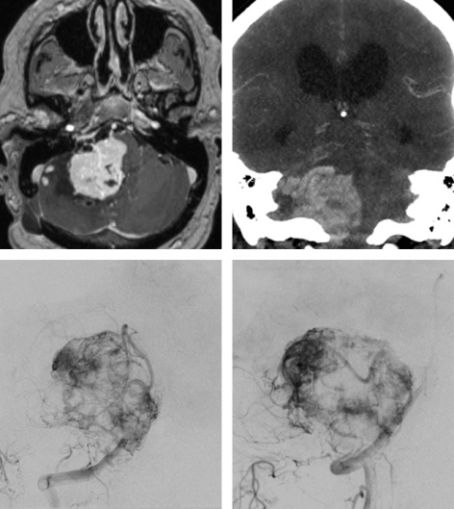

图2. 展示了单纯的脑干区实性肿瘤(左上图)、CT血管成像(右上图)、正位及侧位血管造影(下图)提示了肿瘤的血管范围。这个肿瘤血供丰富,因此操作起来难度较大,应该选择与高血流量脑干AVM相类似的入路而不选择典型小脑半球HB相同的入路。